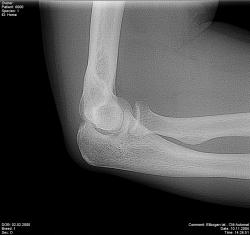

Для диагностики пневмонии, синуситов, травм и переломов, заболеваний суставов и позвоночника необходим рентген. Мы используем современный цифровой рентген, снимки выдаются сразу на месте и распечатываются на специальной фотобумаге. Вас осмотрит врач, установит диагноз, заберет анализы и назначит лечение перелома, выполнит необходимые инъекции, сделает гипс. Мифы и правда о рентгене на дому!